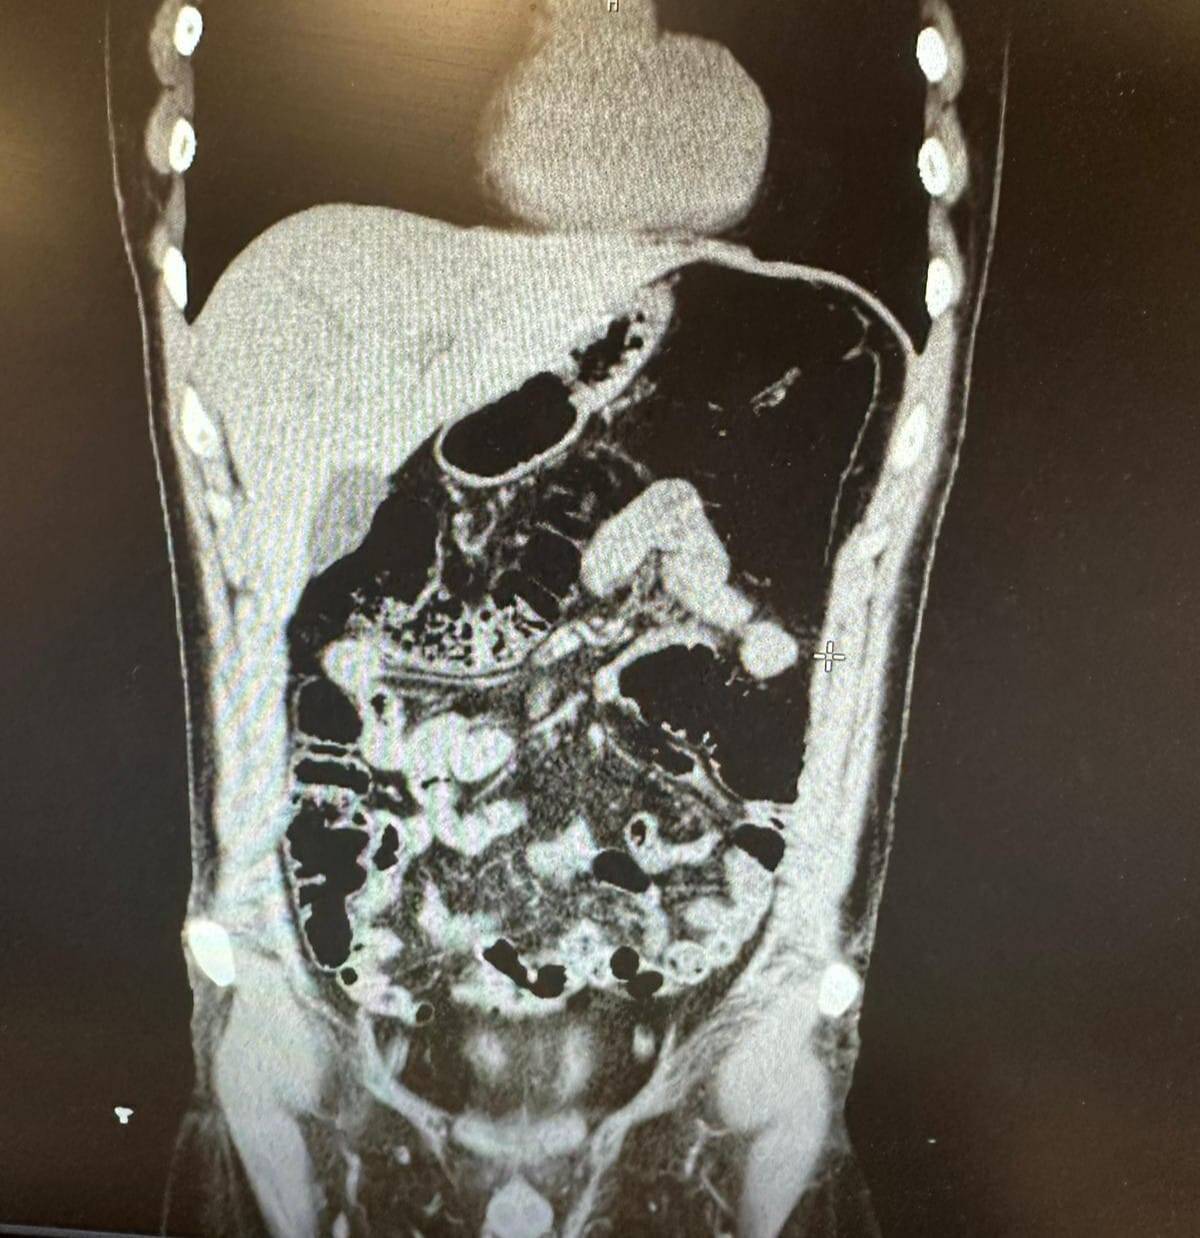

Ekiplerin titizlikle yürüttüğü saha çalışmalarında uyuşturucu kuryeliği yapan İran uyruklu bir şahıs tespit edildi. Polis, şüphelinin Konya’da gizlendiği adresi tespit ederek operasyon düzenledi. Şüpheli ve beraberindeki 4 kişi gözaltına alındı. Şüphelinin uyuşturucu yuttuğunu ifade etmesi üzerine hastaneye kaldırıldı. Şüpheli, 2 gün boyunca polis nezaretinde hastanede gözlem altında tutularak midesinde kapsüller halinde bulunan eroin maddesi doğal yollarla dışarı çıkarıldı.

Konya’da konakladıkları evin tespit edilmesiyle 1’i İran uyruklu 5 şüpheli yakayı ele verdi. İran uyruklu V. F. G.’nin midesinde 300 gram, gizlendiği adreste ise Narkotik köpeği Alex ile yapılan aramada ise toplam 6 parça halinde 1 kilogram eroin, bir miktar metamfetamin ve bir miktar uyuşturucu hap ele geçirildi.